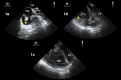

Background: The COVID-19 pandemic has placed an extraordinary strain on healthcare systems across North America. Defining the optimal approach for managing a critically ill COVID-19 patient is rapidly changing. Goal-directed transesophageal echocardiography (TEE) is frequently used by physicians caring for intubated critically ill patients as a reliable imaging modality that is well suited to answer questions at bedside.

Results: Although transthoracic echocardiography can provide the information needed in most patients, there are specific scenarios in which TEE represents the modality of choice. TEE provides acute care clinicians with a goal-directed framework to guide clinical care and represents an ideal modality to evaluate hemodynamic instability during prone ventilation, perform serial evaluations of the lungs, support cardiac arrest resuscitation, and guide veno-venous ECMO cannulation. To aid other clinicians in performing TEE during the COVID-19 pandemic, we describe a set of principles and practical aspects for performing examinations with a focus on the logistics, personnel, and equipment required before, during, and after an examination.

Conclusions: In the right clinical scenario, TEE is a tool that can provide the information needed to deliver the best and safest possible care for the critically ill patients.